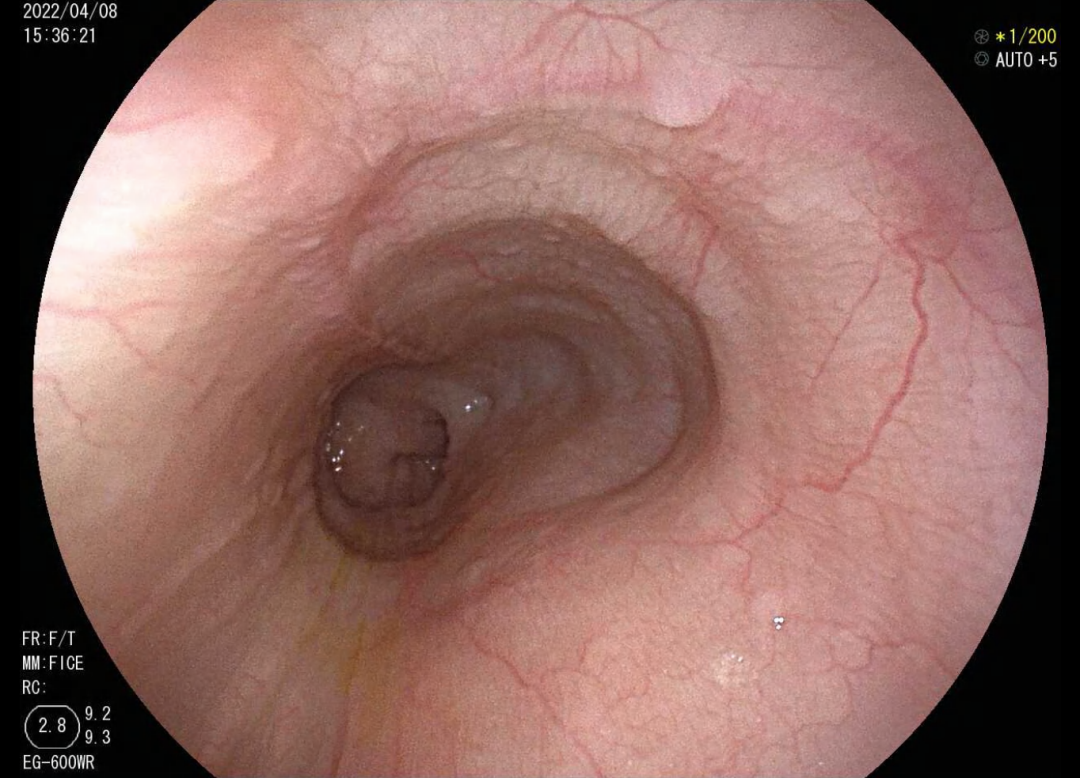

住院后医生为她安排了胃镜检查和上消化道钡剂造影,检查结果提示贲门失弛缓及食管中段憩室。

韩梅病情特殊,消化内科主任李滨教授和副主任肖绪华在详细阅读各项检查报告后,发现患者食管下端呈“鸟嘴样”改变,同时上端分别紧接一个约2.5cm大小的憩室,结合患者病史,明确患者“贲门失弛缓合并食管中段憩室”的诊断。他们认为造成了韩梅多年梗噎和反流的病的原因是:食管下段肌群持续紧缩,蓄积的食物被迫推向多发的憩室,加重憩室的扩张,食管及憩室内食物反流。

胃镜图(左图食管下段扩张,右图食管中段憩室)